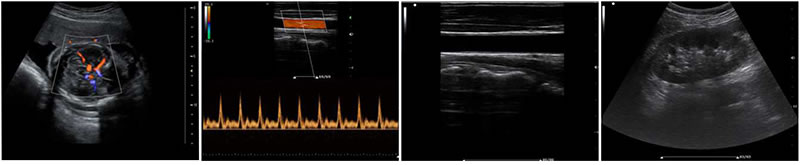

B、C、PW、CW、BCD三功、大角度偏转成像、实时宽景成像、梯形成像(仅支持线阵)、解剖M型、彩色M型成像、组织多普勒成像、3D/4D成像

有效抑制彩色血流闪动噪声,提高血流分辨率和灵敏度

成像模式

·B-模式 ·M-模式 ·THI-模式 ·Color 模式(CFM)

·PDI 模式 ·PW 模式 ·CW 模式